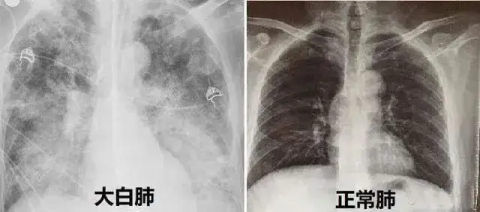

“白肺是肺部影像学表现的一个口语化描述,并不是指肺脏组织实体变成了白色。”焦雅辉介绍,当肺泡里出现炎症或感染,肺泡被渗出液和炎性细胞所填充,CT或者X线检查的射线穿不透,会在影像学上出现白色区域。不仅是新冠病毒,呼吸道合胞病毒、流感病毒等多个病原体和一些细菌都可以引发肺部炎症。

焦雅辉解释,并不是只要肺部出现了炎症就都叫白肺,白肺是比较严重的肺炎表现,一般来讲,白色影像区域面积达70%-80%被称为白肺。这个阶段,患者会出现低氧血症或呼吸窘迫,主要治疗方案是俯卧位通气和给氧治疗。加强原发病的病因治疗,有相当部分的白肺患者可以好转。